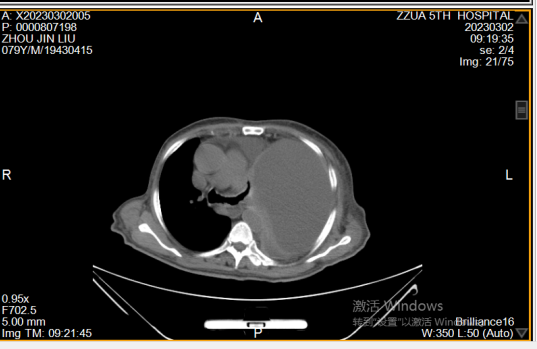

近日,郑州大学五附院呼吸与危重症医学科收治一位79岁 “胸腔积液”男性患者,该患者既往有“支气管哮喘”,此次以“胸闷、气喘20余天,加重2天”为主诉入院,门诊查胸部CT提示左侧大量胸腔积液,左肺压缩不张。如下图: